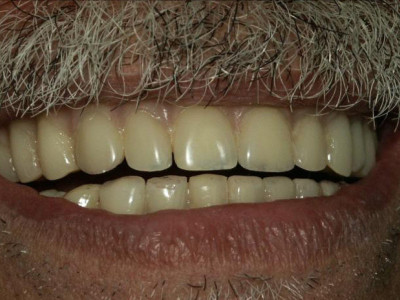

Terminado de Prótesis Hibridas superior e inferior atornillada sobre implantes que van fijas y no se las tiene que quitar el paciente